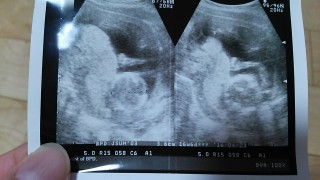

3人目妊娠♡* 何人産んでも初産の様な気持ち(>人<;)健診のドキドキや不安は変わりません。 4週間ぶりの健診^^元気にすくすく育っていました♡安心♡*吐きづわりが早く治るといいな^^一緒に頑張ろうね^^また4週間後に元気な姿を見せてね^^♡ 【性別は次回のお楽しみ】

4週間ぶりの検診。どんどん人間らしくなっていく我が子にすでにメロメロです?性別はやく分かるといいな!